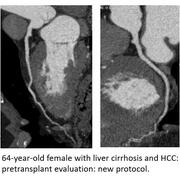

Pre-transplant liver and renal patients: The pre-transplant patients require coronary artery imaging to assess the risk of cardiac ischemia before major surgery such as the solid organ transplant. Unfortunately, standard coronary CTA imaging protocols yield suboptimal image quality in these patients due to their altered hemodynamic status. This results in either a suboptimal assessment of their pre-transplant risk or a need for invasive (and hence risky) imaging protocols such as coronary catheterization.

We developed two coronary CTA protocols tailored for those two distinct groups of patients:

1. Pre-liver transplant patients usually have low ejection fraction, large extracellular space, and portosystemic shunting. Thus, we implemented a protocol with increased IV contrast volume and injection rate in combination with decreased kVp to increase vessel enhancement.

Those protocols have shown that diagnostic CCTAs can be obtained in 90% of high-risk pre-liver and kidney transplant patients and have been incorporated into standard clinical care for pre-solid organ transplant patients.

The successful implementation of this protocol led to the establishment of a new hospital-wide protocol.